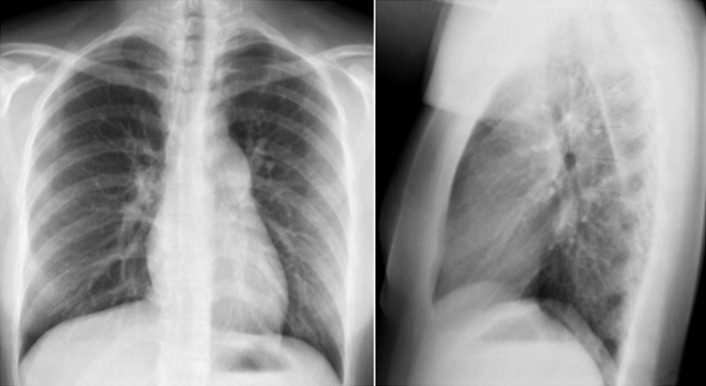

Pulmonic stenosis and dilated cardiomyopathy. The cardiothoracic ratio is increased, and the cardiac contour is globular with multichamber enlargement. There is dilation (poststenotic) of the main pulmonary artery.

Valvular pulmonary stenosis with poststenotic dilation of the main pulmonary artery and with right ventricular enlargement.